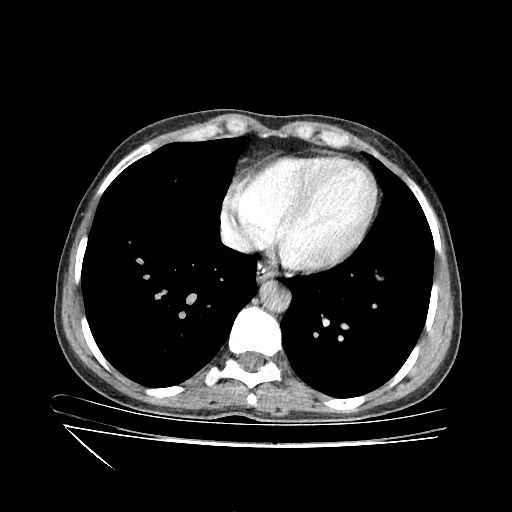

Generated VENOUS CT scan (A→B translation)

Full window (WL 1023.5, WW 4095 β†’ Low βˆ’1024, High +3071)

Mediastinum window (WL 40, WW 400 β†’ Low βˆ’160, High +240)